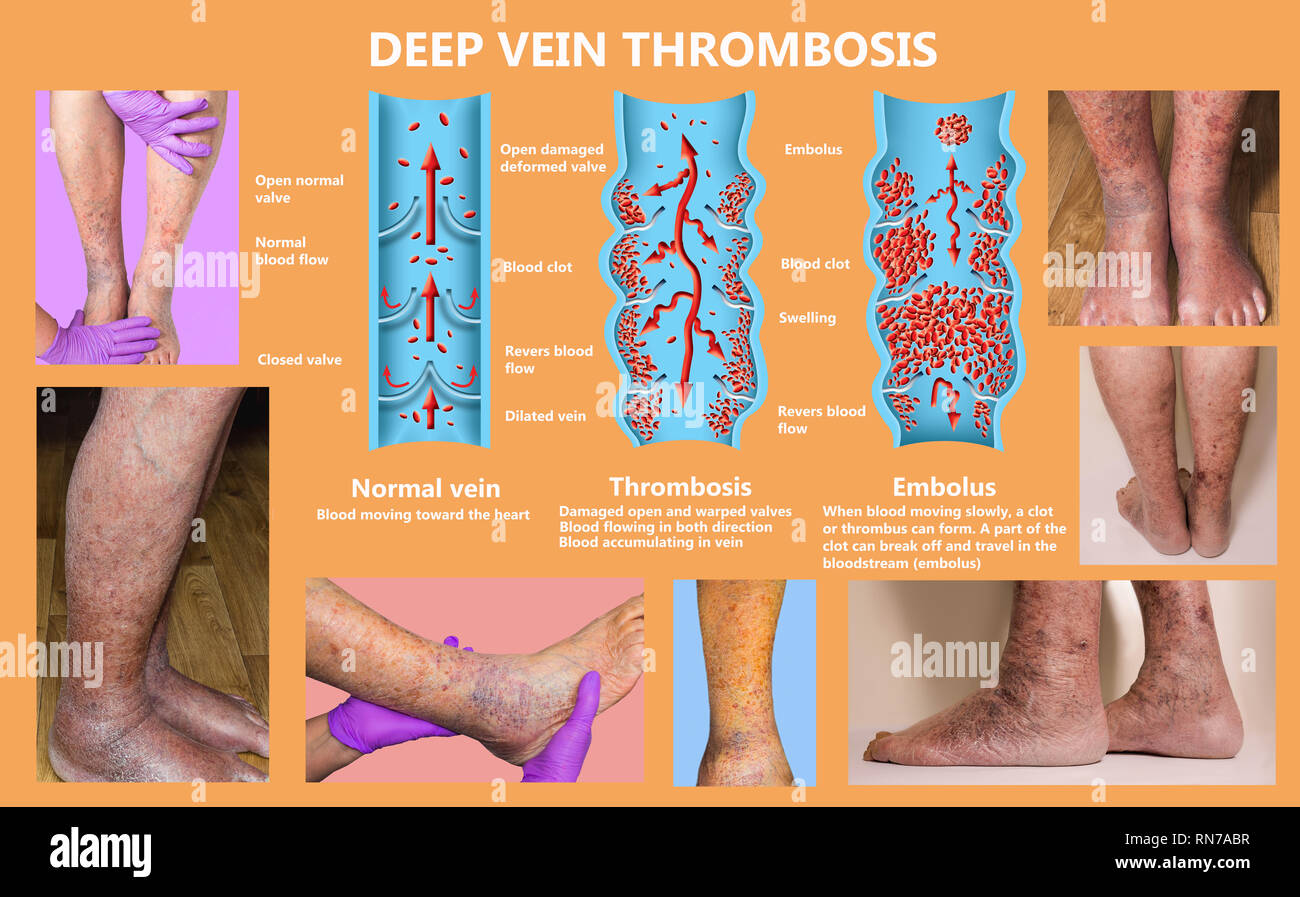

RM2H1FTKC–Syndrome mécanisme, thrombose veineuse profonde ou embolie pulmonaire, thrombose ou PE, thrombose coronaire, illustration du schéma de jambes mâle

RFRN7ABR–Syndrome mécanisme, thrombose veineuse profonde ou d'une thrombose veineuse profonde, embolie pulmonaire, thrombose coronaire, schéma

RFRN7AAX–Syndrome mécanisme, thrombose veineuse profonde ou d'une thrombose veineuse profonde, embolie pulmonaire, thrombose coronaire, schéma